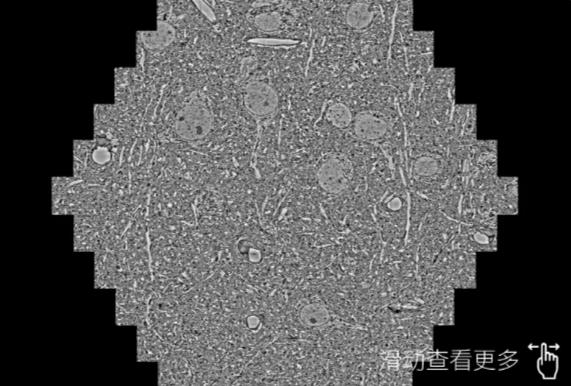

鼠脑切片。左图使用河东蔡司河东扫描电镜MultiSEM706对165μmx143pm面积区域成像,耗时仅需1.5秒。右图为鼠脑切片中30μm区域放大效果。样品由芝加哥大学B.Kasthuri提供。

使用蔡司高速河东扫描电镜MultiSEM对1mm²人脑皮层组织进行高分辨成像,并对其中的各种细胞结构进行三维重构分析。左图展示了2x3mm²组织平面中锥体神经元的三维重构效果。右图显示了局部体积神经元三维重构。图像由哈佛大学chtman实验室提供,渲染图由D. Berger 制作。